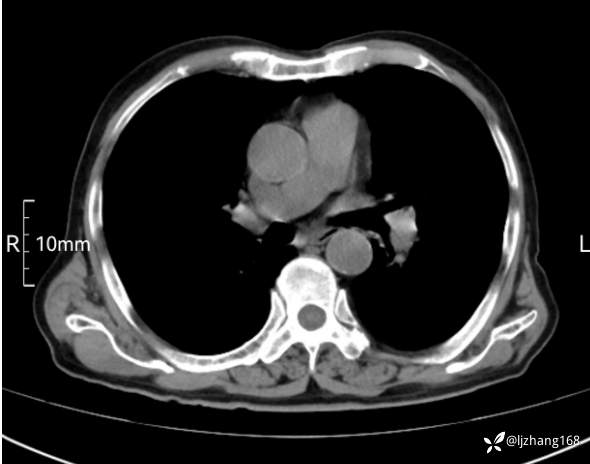

辅助检查:胸部CT:双肺肺气肿,间质性病变,血气分析:PH 7.413, PCO2 29.2mmHg, PO2,81.8mmHg,乳酸 3.3mmol/1,剩余碱-4.0mmol/1,HC03 18.8mmol/1。全血超敏C反应蛋白:超敏C反应蛋白 135.60 mg/L、 白细胞 14x19^9/L,中性粒细胞11.6x10^9/L。